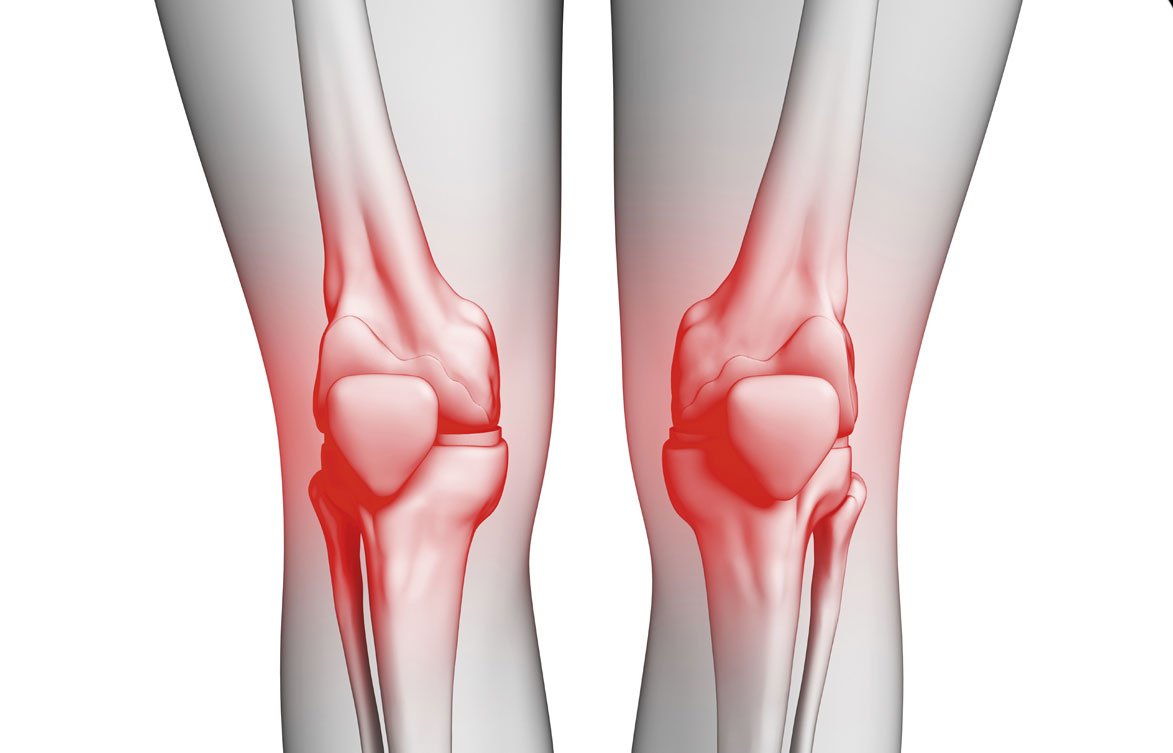

آلام الركبة هي مشكلة شائعة تؤثر على العديد من النساء في مراحل عمرية مختلفة، وتعد واحدة من أبرز المشكلات التي تزعج حياة الكثيرات. يمكن أن يكون ألم الركبة نتيجة لعوامل متعددة مثل التقدم في العمر، السمنة، أو حتى ممارسة الرياضة بشكل مفرط. ومع تطور الأبحاث في مجالات العلاج الطبي، أصبح هناك العديد من الطرق غير الجراحية والفعالة للتعامل مع هذه الآلام. في هذا السياق، يبرز دور دكتور هشام العزازي المتخصص في علاج آلام الركبة عند النساء باستخدام أحدث العلاجات التداخلية.

تختلف أسباب آلام الركبة عند النساء عن تلك التي يعاني منها الرجال، إذ توجد عدة عوامل فسيولوجية وهرمونية تؤثر على صحة المفاصل، وخاصة الركبة. من بين هذه الأسباب:

خشونة الركبة: خشونة الركبة المتقدمة، والتي تصيب العديد من النساء في منتصف العمر، هي حالة شائعة تؤدي إلى تلف الغضاريف التي تغطي مفصل الركبة، مما يسبب الألم والالتهاب.